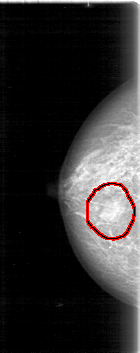

D_4012_1.LEFT_MLO

LEFT_MLO LINES 5386 PIXELS_PER_LINE 2341 BITS_PER_PIXEL 12 RESOLUTION 43.5 NON_OVERLAY

FILE: D_4012_1.RIGHT_CC.OVERLAY

TOTAL_ABNORMALITIES 1

ABNORMALITY 1

LESION_TYPE MASS SHAPE OVAL MARGINS OBSCURED

ASSESSMENT 0

SUBTLETY 5

PATHOLOGY BENIGN

TOTAL_OUTLINES 1

BOUNDARY